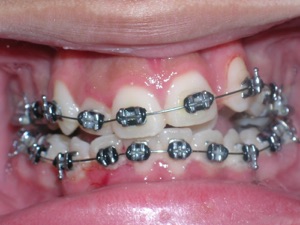

Here’s an example from a young boy who had very significant crowding. One can see that the canines on top and bottom are blocked out. There was also an overbite. The combination made the case challenging. Watch.